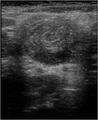

Evaluation

- Longitudinal view shows a dilated intussuscipiens containing the intussusceptum

- This forms three parallel hypoechoic layers separated by hyperechoic zones

- Pseudokidney sign can be seen if mesentery is only on one side of the bowel

- Short axis shows a target sign of three parallel hypoechoic areas separated by hyperechoic zones